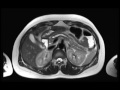

Benign Pancreatic Duct Stricture

Multiple MR images demonstrate a dilated pancreatic duct with abrupt narrowing and cough at the level of the pancreatic head/neck. No discrete mass was identified, and this represents a benign pancreatic stricture related to prior chronic pancreatitis.